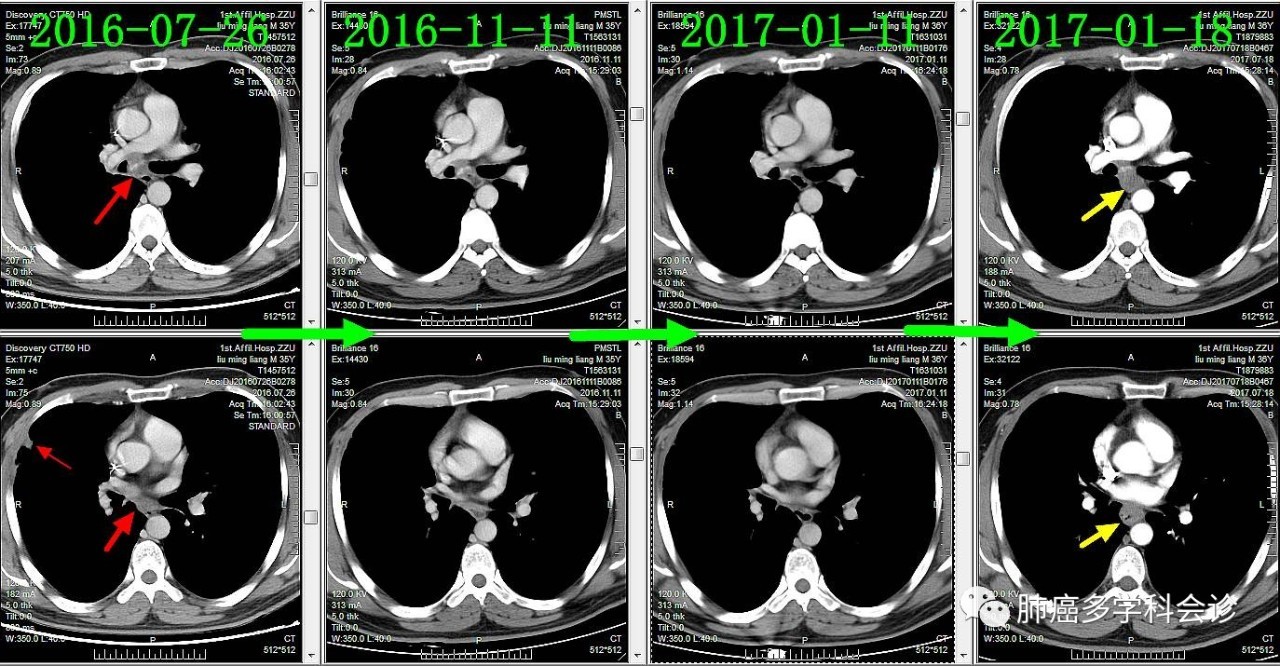

下面通过对比治疗过程中胸部CT变化,展示胸部肿瘤此消彼长的过程:

纵隔肿大淋巴结逐渐缩小

胸膜转移灶消失

食管转移灶从小到大

食管不是肺癌的常见转移部位,容易被忽视。回顾该患者以往的胸部 CT 可见:在纵隔淋巴和原发灶逐渐退缩过程中,食管转移却逆势发展起来,反映了肿瘤对治疗反应的异质性。